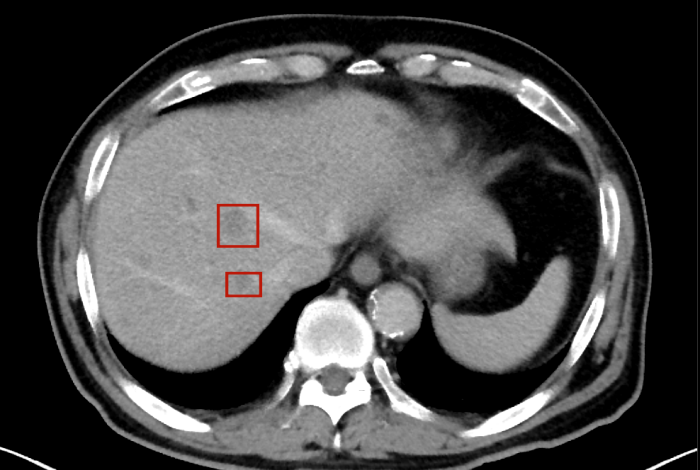

術(shù)后,萬(wàn)秀萍為黃先生做進(jìn)一步的檢查,腹部磁共振(MRI)檢查顯示:肝臟區(qū)域出現(xiàn)了轉(zhuǎn)移病灶的陰影。

轉(zhuǎn)移病灶的陰影

目前,黃先生的腫瘤活動(dòng)已得到有效抑制,肝臟轉(zhuǎn)移灶未見爆發(fā)性進(jìn)展,病情整體保持穩(wěn)定。